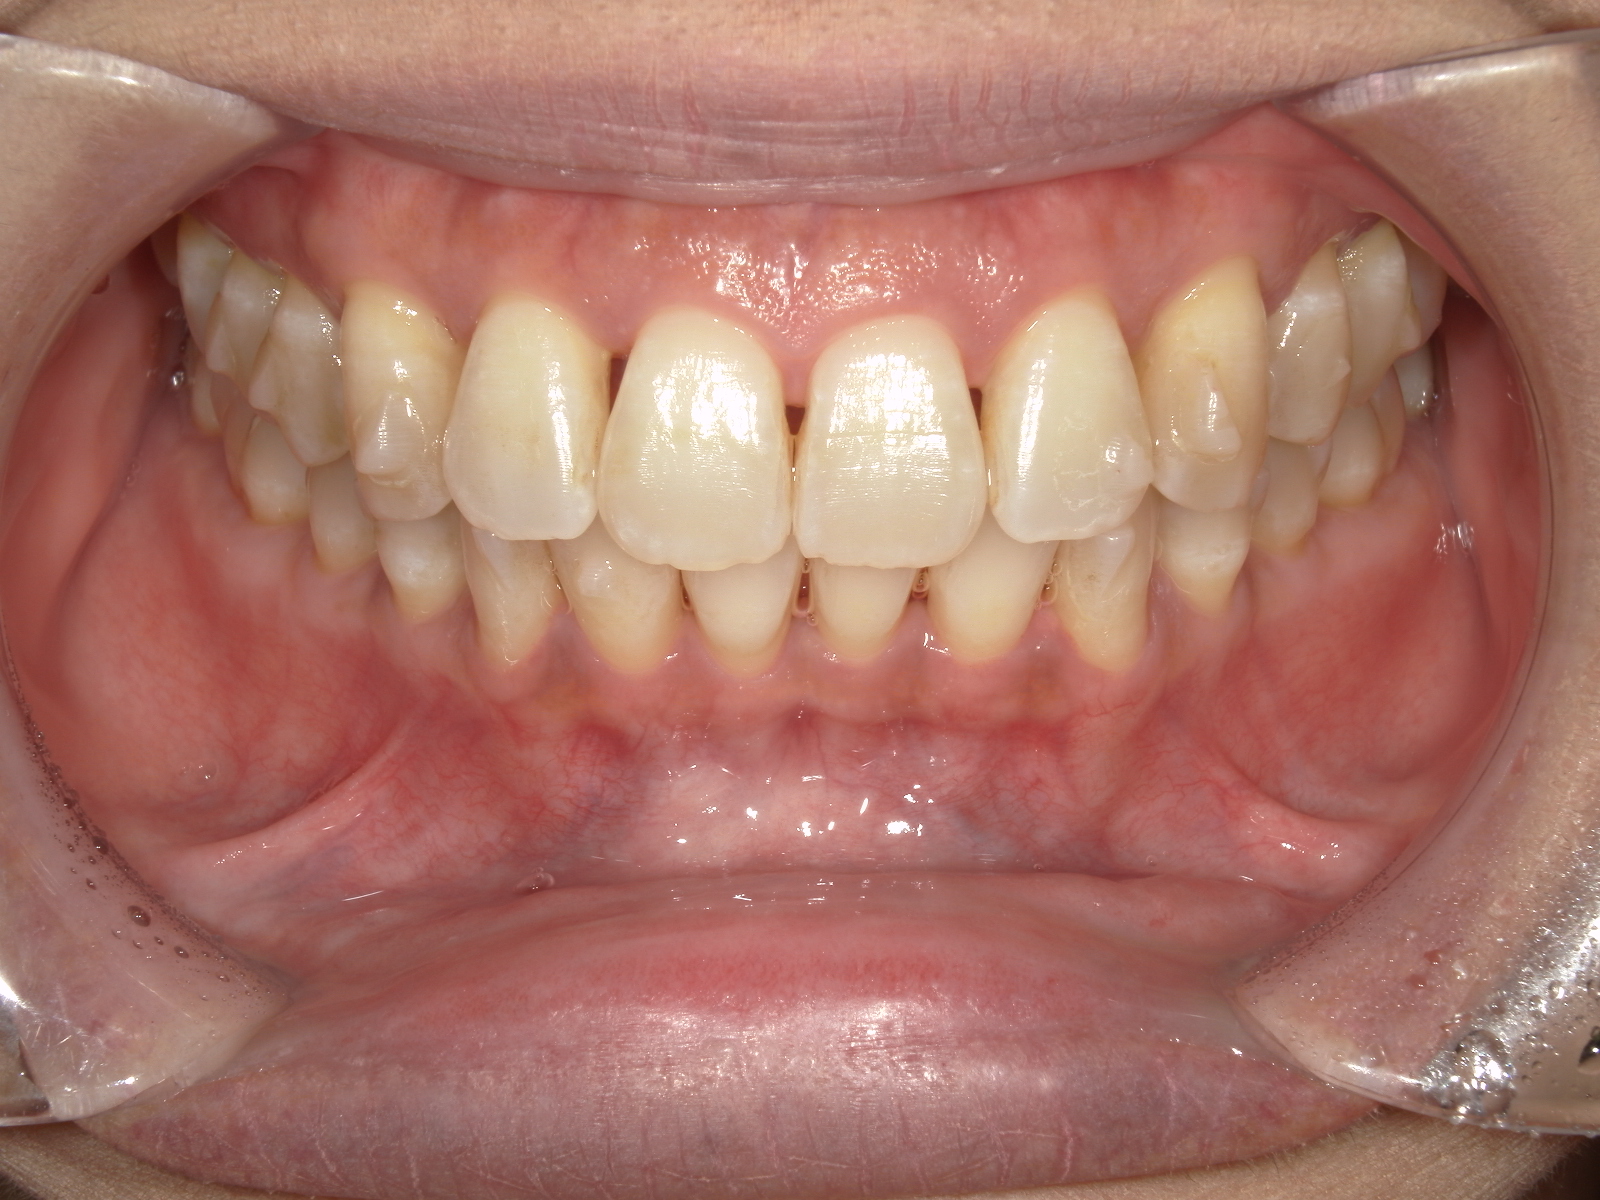

After

5ヶ月経過の口腔内写真比較

最近、鏡を見ると前歯の並びが前より揃ってきているのが分かります。

「本当に動いているのかな?」と半信半疑だった頃と比べると、写真を見比べてみても確かに少しずつきれいになってきていて、嬉しい気持ちになります。